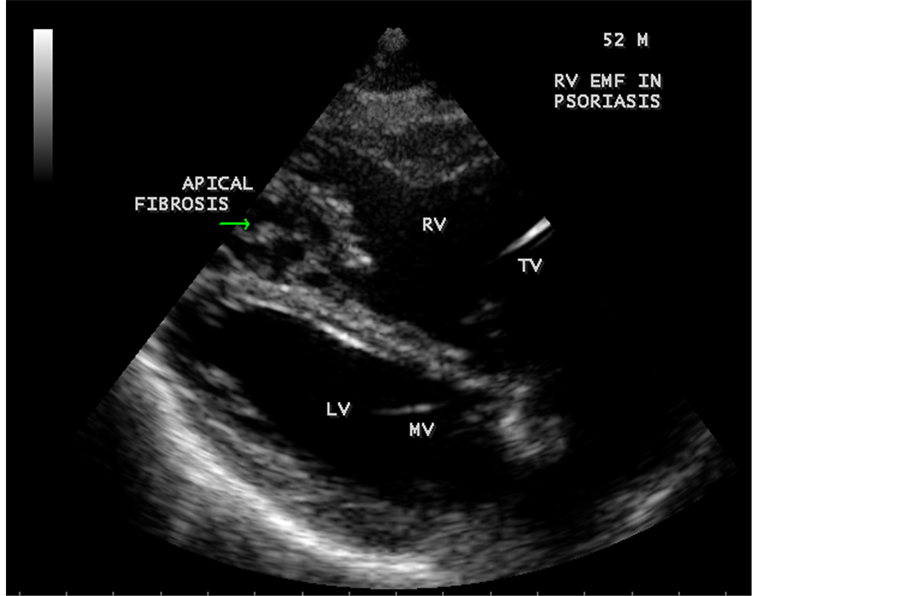

Transthoracic echocardiography revealed strong fibrous strands appearing as “finger like projections” or “cobra-head” appearance in the right ventricular apex due to fibrosis of muscular trabeculae, suggesting right ventricular endomyocardial fibrosis as shown in Figure 3 to Figure 7.

Figure 6. Dense fibrosis in RV apex in Psoriasis in a 52-year-old male.

3.3. Echocardiographic Features

Today echocardiography is used as the screening tool at the community level as the diagnosis of EMF could be confirmed at the bedside. Echocardiography accurately assesses the pathological abnormalities of chronic disease and it is the gold standard technique for the diagnosis of EMF [36] . It reveals dense endomyocardial echocardiograms along different parts of the mural and valvular endocardium and AV valve dysfunction [37] as shown in Figure 3 to Figure 7, Figure 10 to Figure 15, Figure 17, Figure 18, Figure 20 to Figure 75 and Figure 78 to Figure 84. The typical feature of EMF is the obliteration of trabecular portion of the ventricle and in advanced cases, there is shrinkage of the cavities creating an apical notch, regurgitation, slow flow with spontaneous echo contrast as in Figure 36 and considerable pericardial effusion. Similar to apical notch of right ventricle, a right atrial notch is well seen as contraction (or retraction) of tricuspid annulus as in Figure 41 and right atrial notch as in Figure 42 and Figure 43, indicating the retraction of right atrial cavity as a peculiar feature of right ventricular EMF. Biventricular enlargement as shown in Figure 41 and biatrial